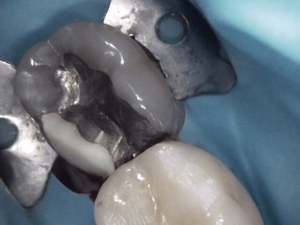

Before and After Treatments

Gordon Street Dental Success Stories in Guelph

Many Patients have allowed us to show what we’ve done for them. Please feel free to look at what we’ve done for them, as well as envision what we can do for you.

Image Grid Title